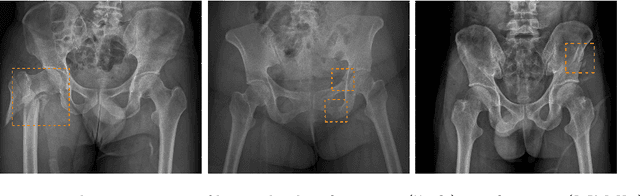

Hip and pelvic fractures are serious injuries with life-threatening complications. However, diagnostic errors of fractures in pelvic X-rays (PXRs) are very common, driving the demand for computer-aided diagnosis (CAD) solutions. A major challenge lies in the fact that fractures are localized patterns that require localized analyses. Unfortunately, the PXRs residing in hospital picture archiving and communication system do not typically specify region of interests. In this paper, we propose a two-stage hip and pelvic fracture detection method that executes localized fracture classification using weakly supervised ROI mining. The first stage uses a large capacity fully-convolutional network, i.e., deep with high levels of abstraction, in a multiple instance learning setting to automatically mine probable true positive and definite hard negative ROIs from the whole PXR in the training data. The second stage trains a smaller capacity model, i.e., shallower and more generalizable, with the mined ROIs to perform localized analyses to classify fractures. During inference, our method detects hip and pelvic fractures in one pass by chaining the probability outputs of the two stages together. We evaluate our method on 4 410 PXRs, reporting an area under the ROC curve value of 0.975, the highest among state-of-the-art fracture detection methods. Moreover, we show that our two-stage approach can perform comparably to human physicians (even outperforming emergency physicians and surgeons), in a preliminary reader study of 23 readers.